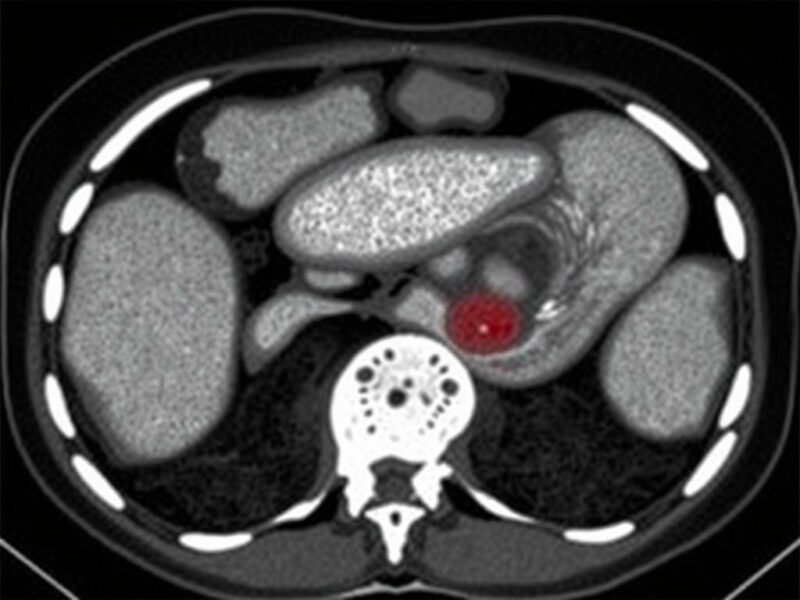

La tomografía computarizada (TAC) con contraste es la prueba de elección en adultos para caracterizar un absceso apendicular. La TAC permite medir el tamaño de la colección, localizar con precisión su relación con estructuras vecinas, detectar gas libre y planificar un drenaje percutáneo si procede. Además, la TAC valora la presencia de apéndice perforado, complicaciones y condiciones concomitantes. La resonancia magnética (RM) puede ser útil en embarazadas cuando se requiere mayor definibilidad sin radiación, aunque su disponibilidad es menor.

Interpretación práctica de la TAC

La TAC no solo confirma la presencia de un absceso, sino que aporta detalles críticos: tamaño de la colección, presencia de septaciones, proximidad a la pared abdominal (lo que facilita un abordaje percutáneo), y si existe gas intralesional que puede indicar infección por bacterias productoras de gas. Un absceso pequeño (p. ej., <3 cm) puede resolverse con antibióticos solos en algunos casos, mientras que colecciones mayores o multiloculadas suelen requerir drenaje. La TAC también ayuda a diferenciar otras patologías que imitan el absceso apendicular, como diverticulitis, abscesos ováricos o procesos pélvicos en mujeres.